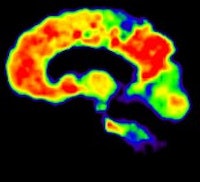

In recent years, both FDG and PiB have become more prominent biomarkers in the diagnosis of several forms of dementia, Ossenkoppele noted. PiB is designed to detect deposits of amyloid plaque in the brain, which have been associated with the onset of Alzheimer's disease. FDG measures metabolic activity of the brain at rest and has been used to distinguish between several forms of dementia.

Researchers then proceeded to the PET scans. First, patients were imaged with PiB for 90 minutes to obtain parametric images of the biomarker binding to potential clusters of amyloid. FDG-PET scans were then conducted 45 to 60 minutes after injection and lasted for 15 minutes. Standardized uptake value (SUV) ratios were calculated throughout the brain.

PiB-PET scans were positive in 40 (61%) of 66 patients with clinical Alzheimer's and in five (28%) of 18 patients with clinical frontotemporal dementia. FDG SUV patterns matched the clinical diagnosis in 58% of patients with Alzheimer's and 33% of patients with clinical frontotemporal dementia, the authors noted.